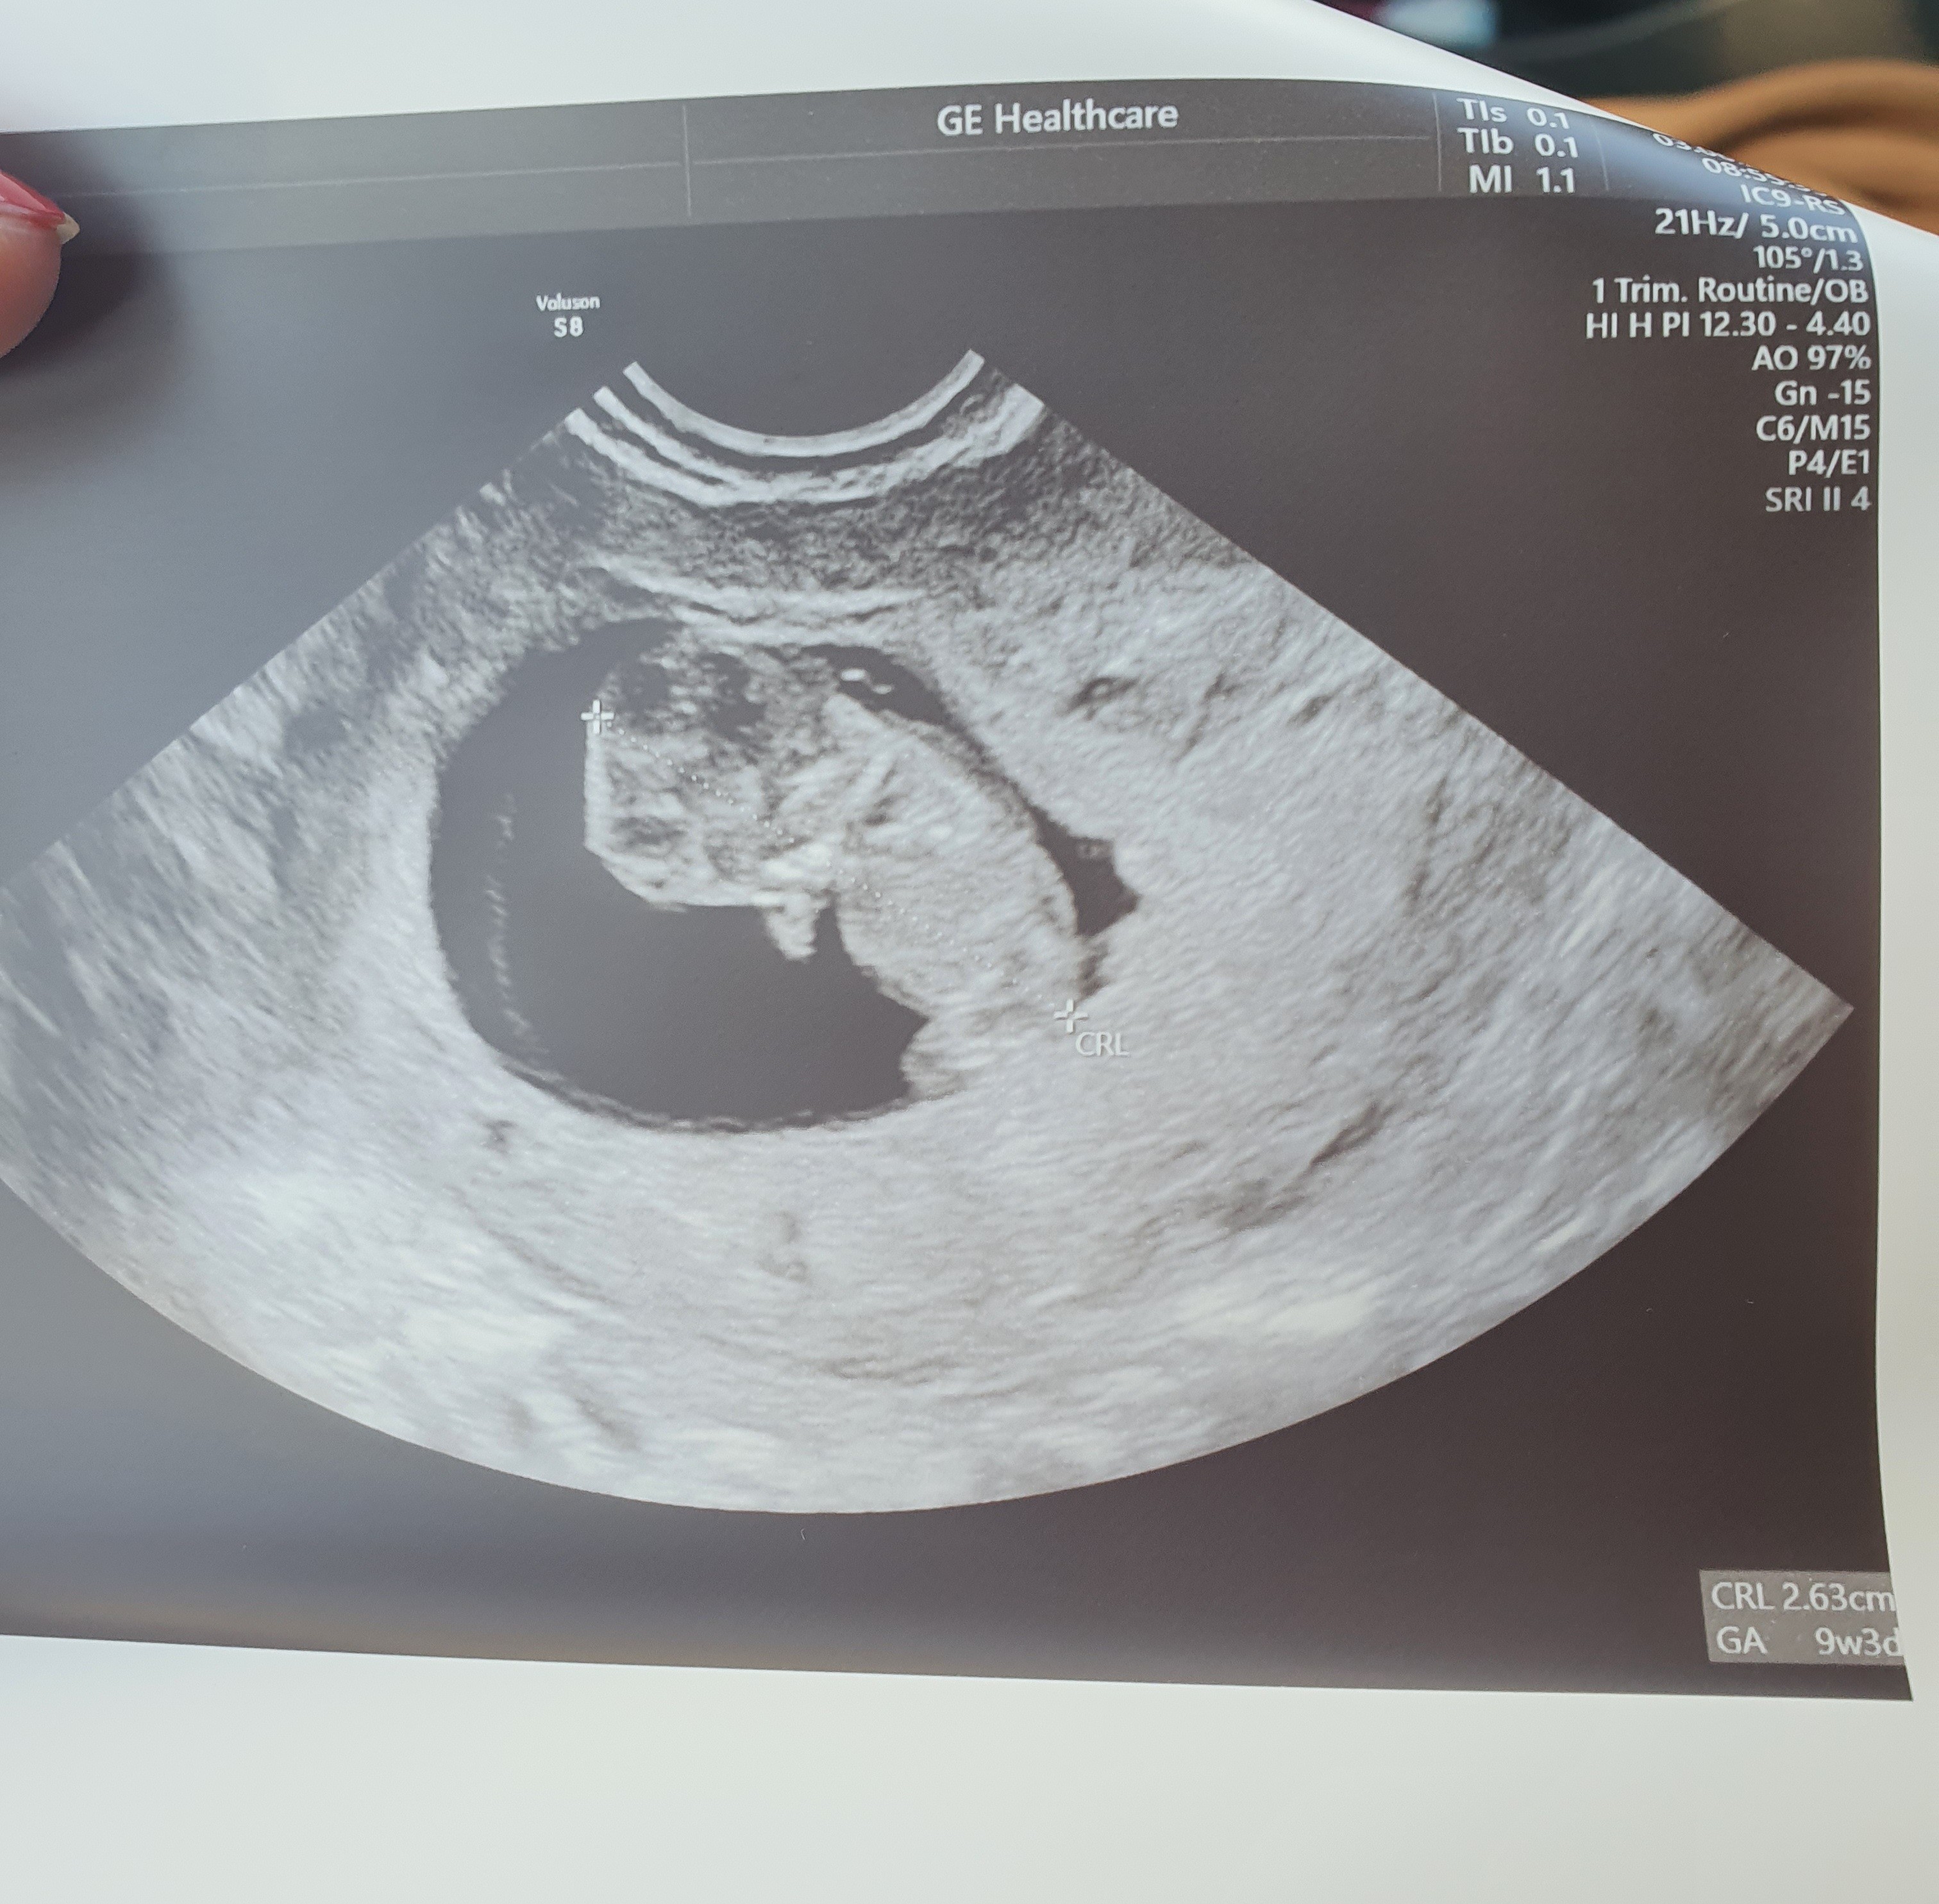

Nie mam jakichś szczególnych objawów, co dodatkowo mnie stresowało, zero mdłości, ból piersi delikatny od samego początku ciąży, jedynie co, to duża senność i zmęczenie. Wczoraj piersi przestały bolec mnie całkowicie, są jedynie powiększone. Oczywiście ustanie tego i tak minimalnego bólu bardzo mnie wystraszyło, przepłakałam cały dzień, po czym umowilam się na prywatna wizytę. Szlam na nią ze łzami w oczach, przekonana o tym, że usłyszę, że to już koniec naszej ciążowej przygody. Co zobaczyłam? 2,4 cm człowieczka, FHR 174, machającego nóżkami i rączkami

pęcherzyk ciążowy również przestał być zmartwieniem, wyglada nareszcie normalnie. Dzisiaj 9+3

Mam nadzieję, że limit nieszczęść został już wyczerpany, za 3 tygodnie prenatalne. Dodaję zdjęcie naszego największego skarbu z wielką nadzieją, że na przełomie roku weźmiemy go w swoje ramiona